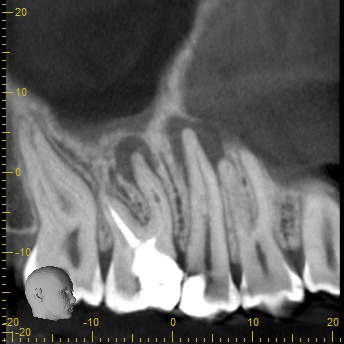

• Rápido – Cómodo – Eficaz: Las imágenes obtenidas con nuestros equipos son altamente detalladas, mostrando los tejidos duros sin perder calidad.

Podemos analizar la posición y orientación de estructuras críticas como los nervios, las raíces dentales, los senos paranasales y la nariz, lo que ayuda a lograr un diagnóstico lo más preciso posible. Con nuestra tecnología de imagen avanzada, tu odontólogo podrá monitorear la estabilidad a largo plazo de tus restauraciones dentales, de esta forma se podrá obtener el resultado estético que deseas con tu tratamiento.